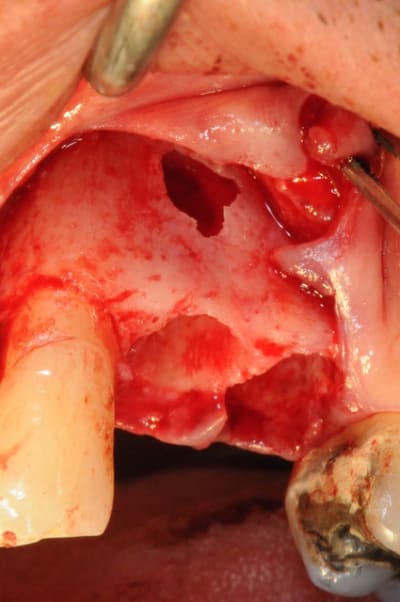

tiens voici des photos de ce matin...

patient avec kyste +++ aux apex et fenestration

je n'implante pas

je comble au Graftec

je met une membrane

je referme

8 mois après,

je vais implanter

comme je suis curieux, j'ouvre large et je regarde;

c'est décevant,le volume est là mais l'os n'est pas génial.

voilà pour les photos...

pendant que je forais, et le patient le sentait également, je sentais et entendais les particules de graftec.

en plus au bout de 8 mois j'aurai espéré trouver quelque chose de mieux non ?